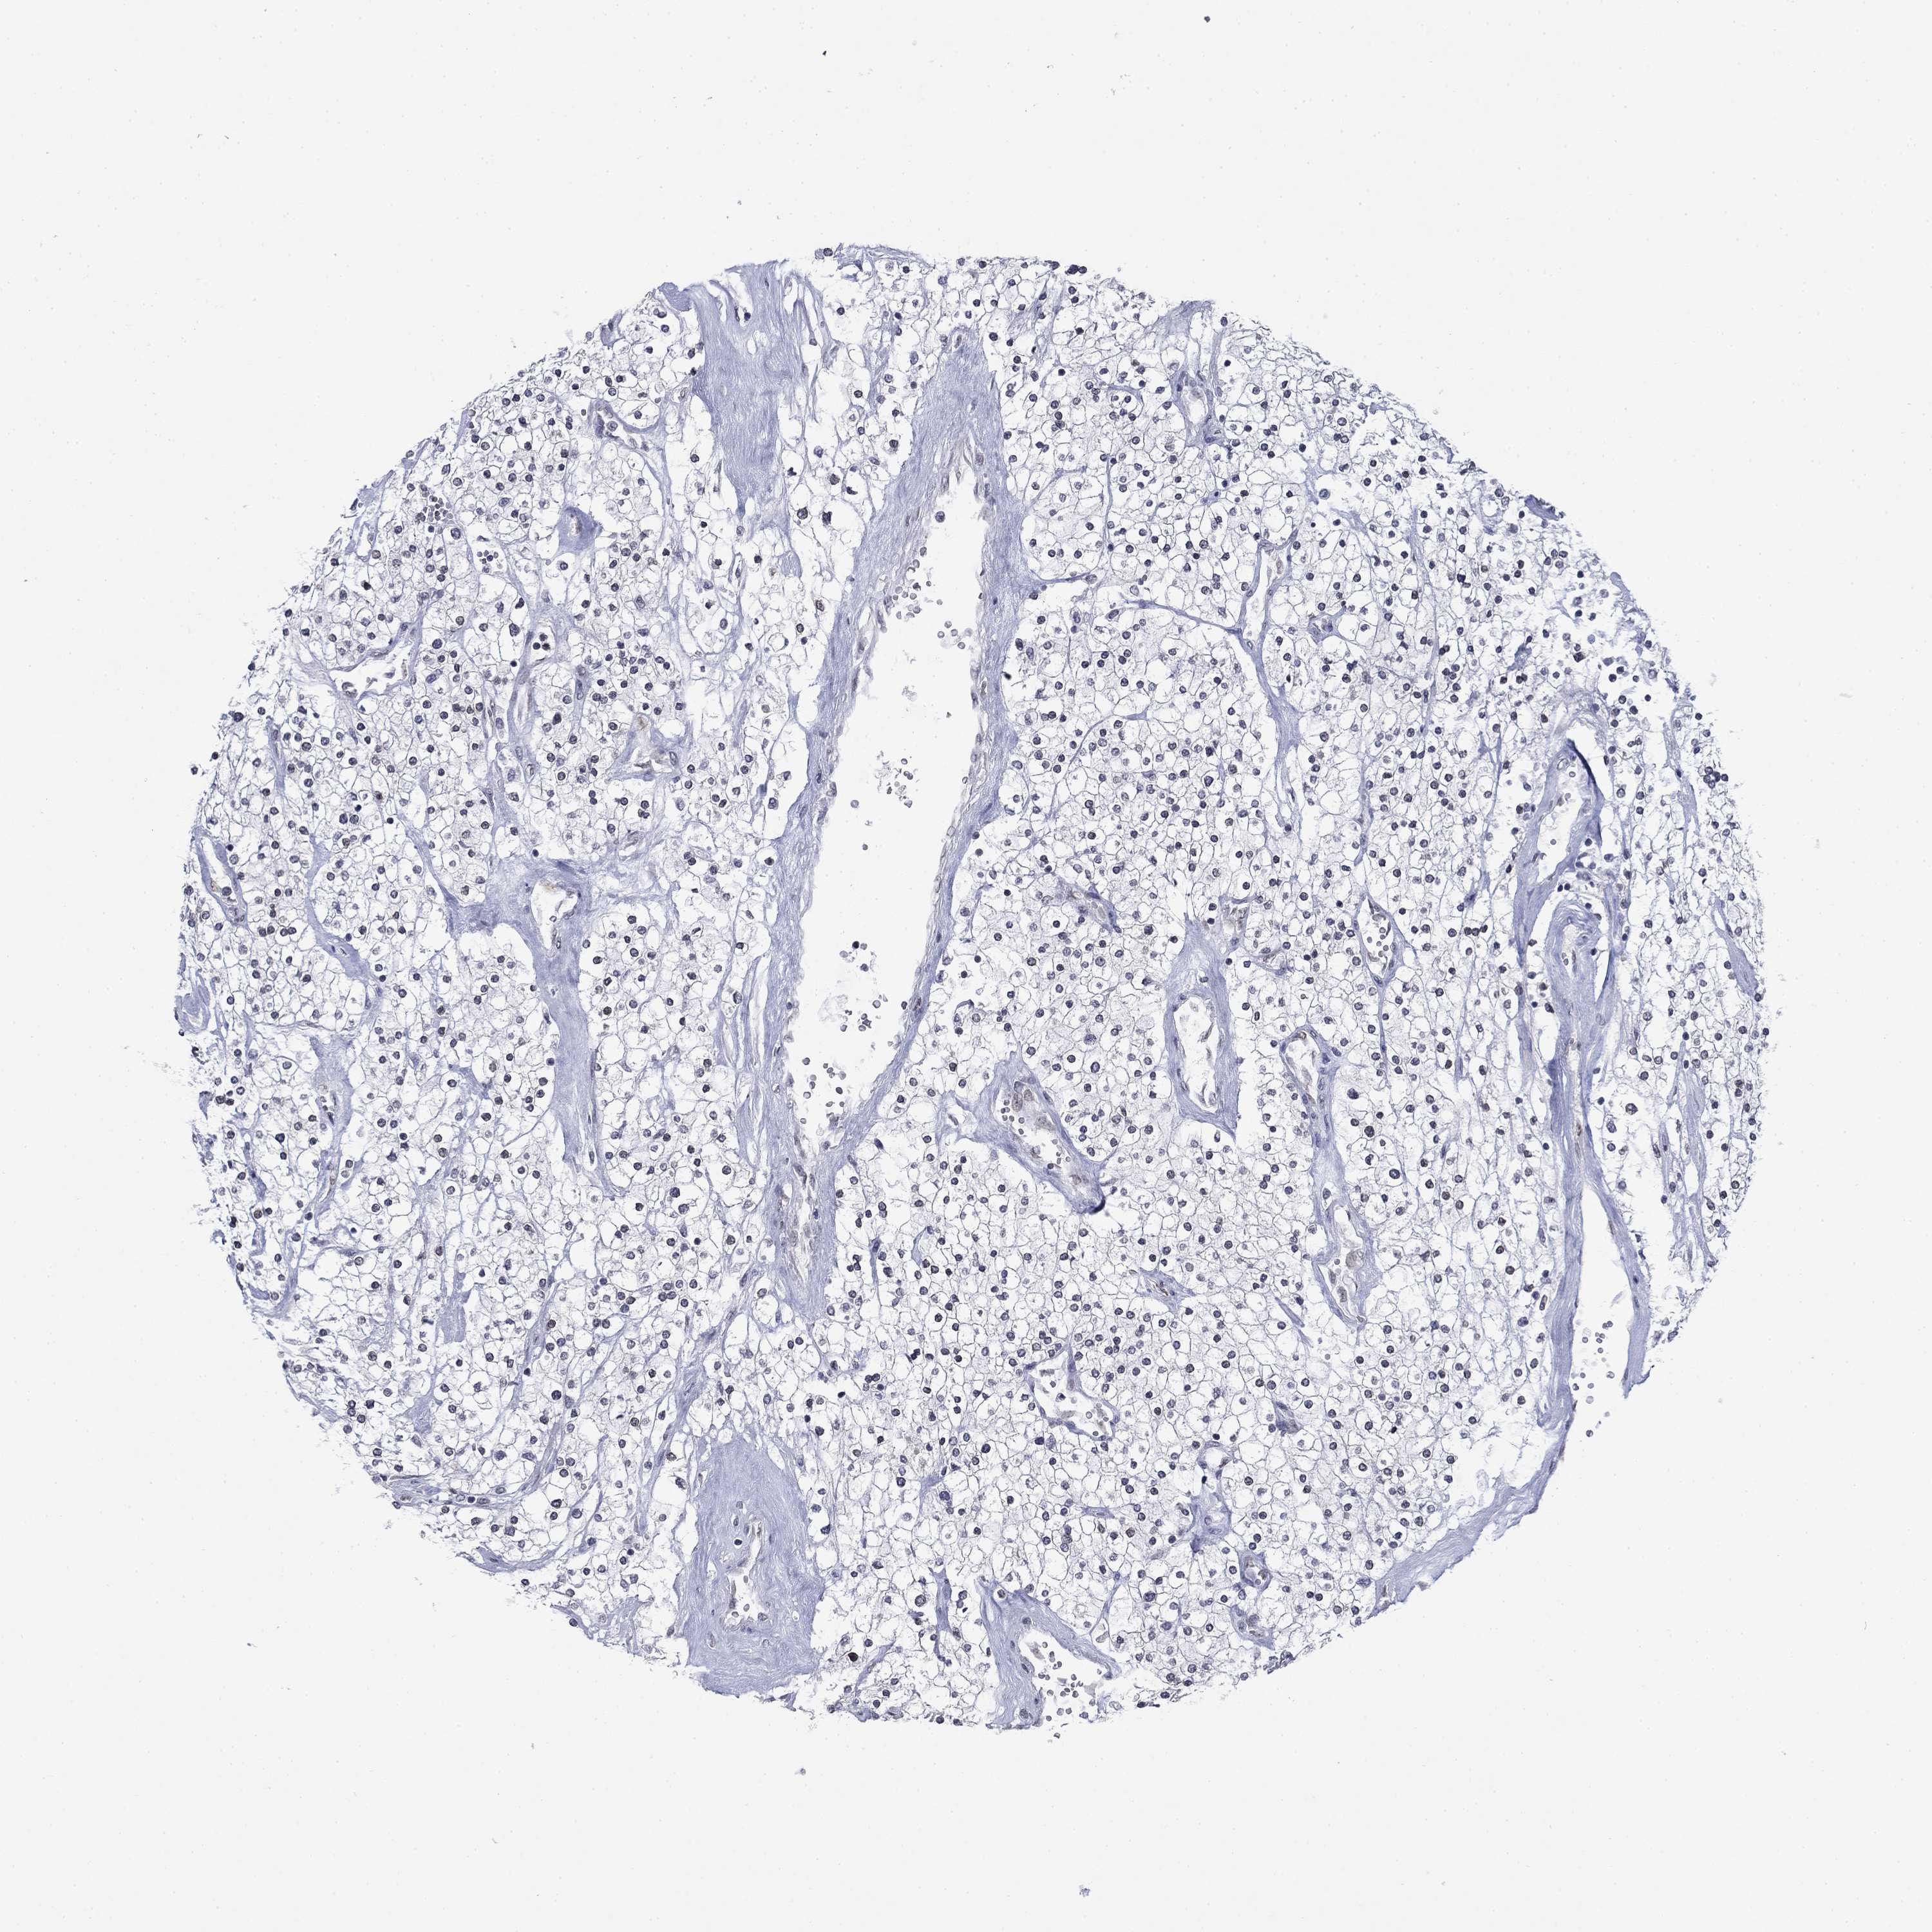

CANCER RENAL CANCER Show tissue menu

KICH TCGA KIRC TCGA KIRC VALIDATION KIRP TCGA PROTEIN RCC CPTAC PROTEIN EXPRESSION